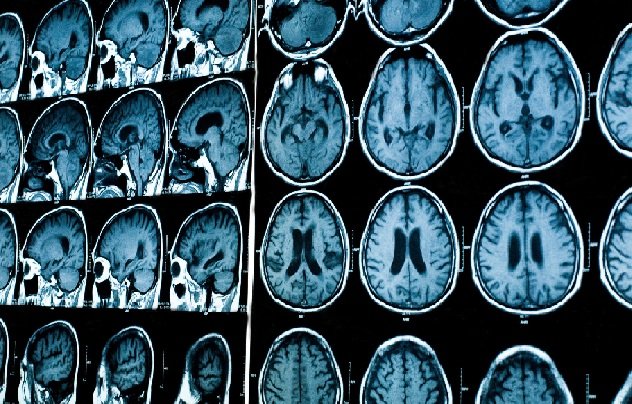

Now, scientists have detected two new biological strands of MS using AI, a simple blood test and MRI scans. Experts said the “exciting” breakthrough could revolutionize treatment of the disease worldwide.

The sNfL results and scans of the patients’ brains were interpreted by a machine learning model, called SuStaIn. The results, published in medical journal Brain, revealed two distinct types of MS; early sNfL and late sNfL.

In the first subtype, patients had high levels of sNfL early on in the disease, with visible damage in a part of the brain called the corpus callosum. They also developed brain lesions quickly. This type appears to be more aggressive and active, scientists said.

In the second subtype, patients showed brain shrinkage in areas like the limbic cortex and deep grey matter before sNfL levels went up. This type seems to be slower, with overt damage occurring later.